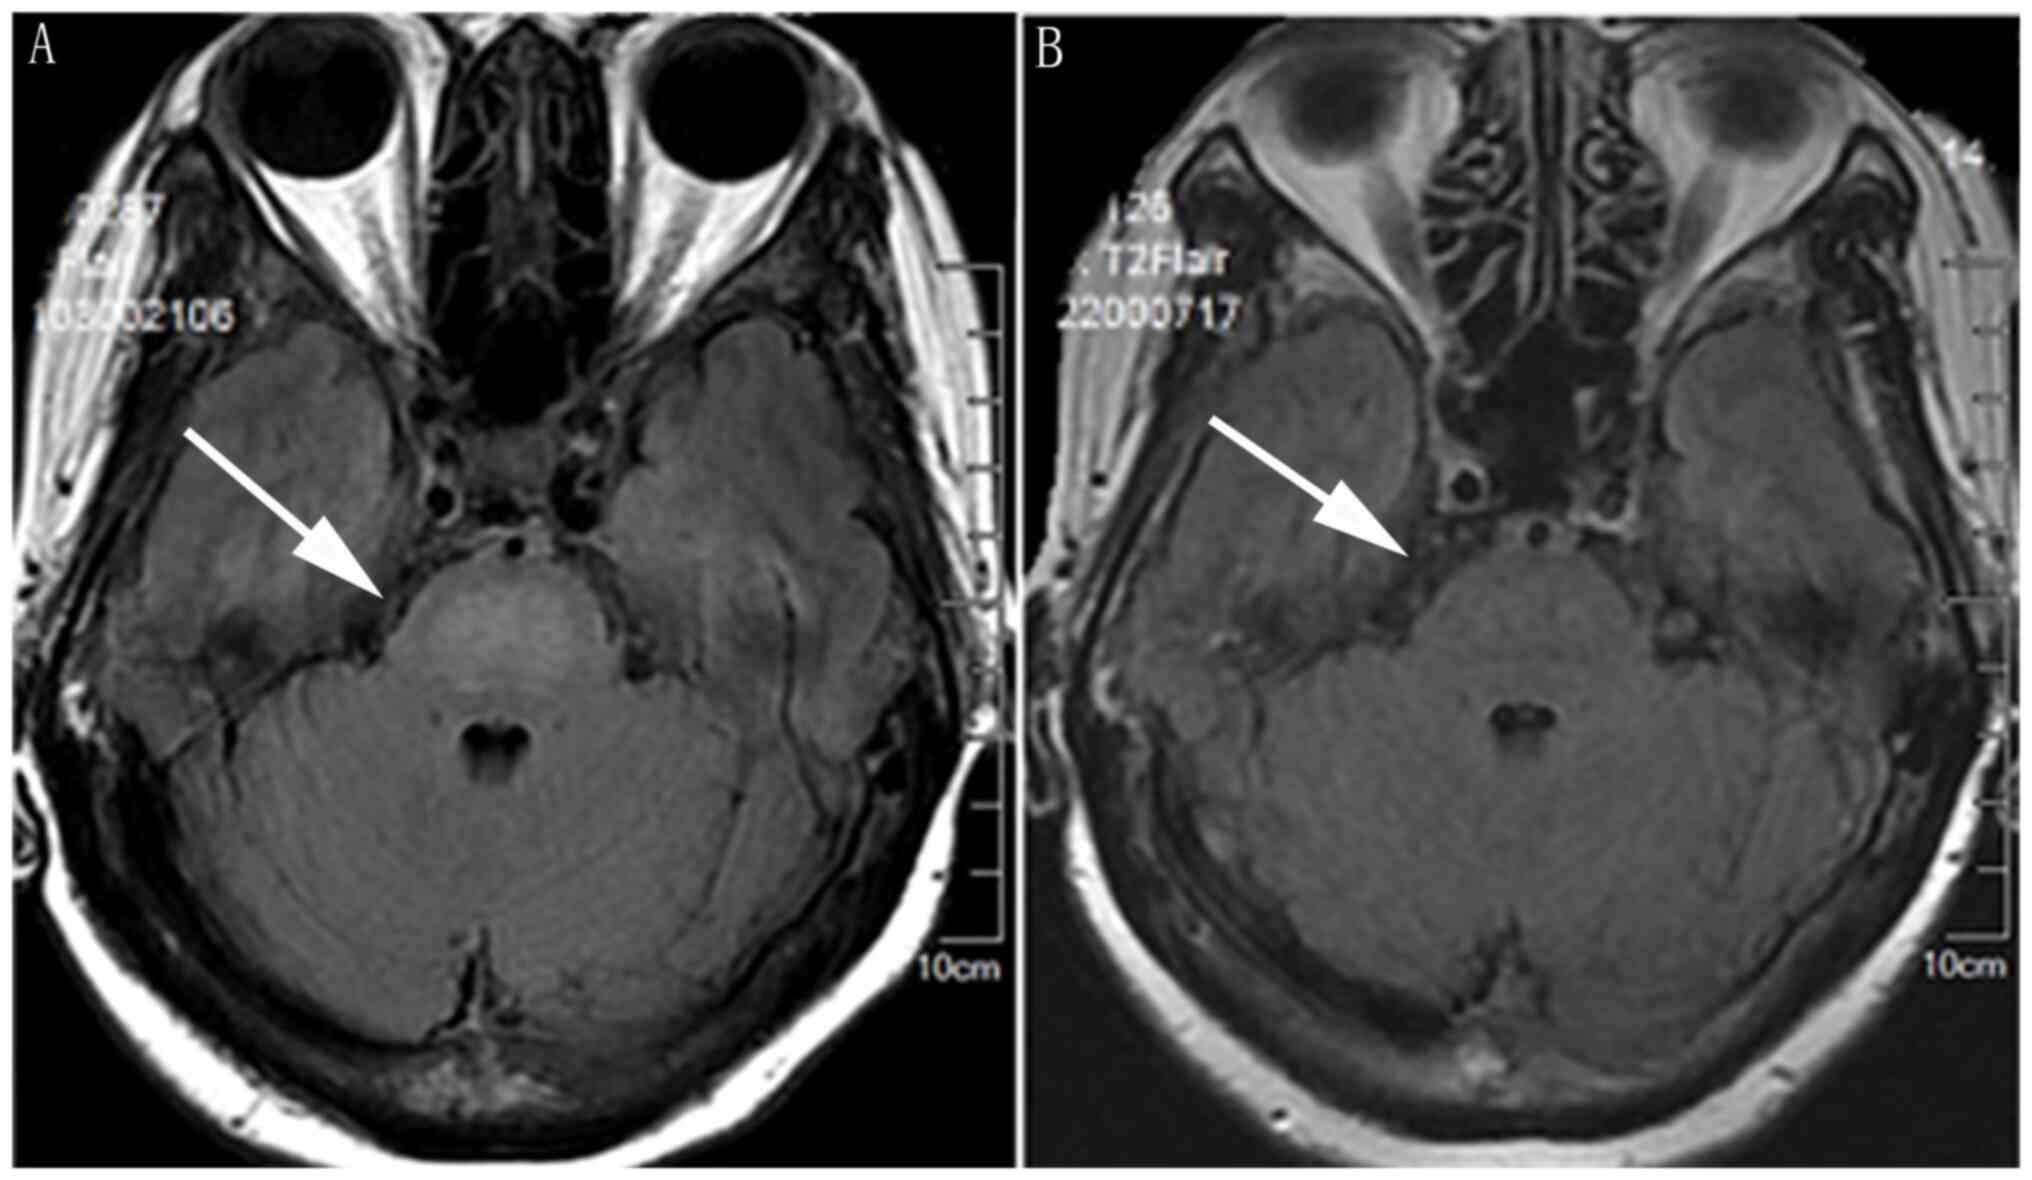

The main laboratory findings are shown in Table I and suggest Epstein-Barr virus (EBV) infection. An ophthalmologist diagnosed xerophthalmia. Bone marrow biopsy samples were positive for CD20 (Fig. 1) and BCL2 and C-myc large cells were identified within vascular spaces, resulting in a diagnosis of double-expression IVLBCL. Immunostaining also revealed that the tumour cells were positive for PAX-5, CD31, CD34, CyclinD1 and Mum1 (Fig. S1), and negative for CD10, BCL6 and CD30; the Ki-67 index was 80%. Flow cytometric analyses of bone marrow revealed positivity for CD20, CD22, CD79b and lambda chains and were negative for CD38, CD138 and kappa (Fig. S2). In addition, positron emission tomography/computed tomography (PET/CT) showed splenomegaly and hypermetabolism, and bilateral lung and bone marrow diffuse hypermetabolism, resulting in a diagnosis of IVLBCL before bone marrow biopsy (Fig. 2). Our patient thus met the five diagnostic criteria for hemophagocytic lympho-histiocytosis (HLH), namely fever, splenomegaly, cytopenia, ferritin ≥500 ng/ml, sCD 25 ≥2,400 U/ml and a bone marrow sample showing hemophagocytes (Fig. 1) (8). Cranial magnetic resonance imaging (MRI) revealed a hyperintense lesion in the central pons (Fig. 3). Thyroid ultrasound indicated hypoechoic thyroid nodules. Papillary thyroid carcinoma (PTC) was diagnosed by fine needle aspiration biopsy (Fig. 1). Immunofixation electrophoresis displayed M proteins positive and IgG kappa light chains (Fig. S3). Next-generation sequencing of bone marrow yielded mutations for the genes of DNMT3A exon13, DNMT3A exon8, FAT1 exon6 and CCND1 exon3. Nucleic acid extraction was performed using the Blood Genomic DNA Extraction Kit (0.1-1 ml; cat. no. YDP348-03; Tiangen Biotech Co., Ltd.). Nucleic acid quality inspection was performed using a NANODROP ONE (Thermo Fisher Scientific, Inc.) to measure the preliminary DNA concentration, A260/280 and A260/230, where A260 is the absorption wavelength of the highest absorption peak of nucleic acid and A280 is the absorption wavelength of the highest absorption peak of protein. A230 is the absorption wavelength of the highest absorption peak of carbohydrates.

A literature search revealed 8 previously reported cases of IVLBCL that involved the thyroid (9-16) (Table II). These patients presented with diverse symptoms and had poor prognoses. IVLBCL and PTC occurred concurrently in only 1 of these patients (10). In that patient, IVLBCL was initially diagnosed by PET/CT and subsequently confirmed by bone marrow biopsy. In our patient, fine needle aspiration biopsy of the thyroid revealed only PTC. PET/CT showed thyroid and lung hypermetabolism. The decrease in PET/CT metabolism after chemotherapy suggested that IVLBCL may had invaded the thyroid and lung. It was nto possible to confirm this because the patient did not undergo total thyroidectomy or lung biopsy. It has been reported that, even in the absence of neurological symptoms, ~90% of patients with IVLBCL have abnormalities on pre-treatment brain MRI and that hyperintense lesion in the pons on T2WI are potentially of diagnostic value (17). No brain lesions were definitively diagnosed because brain biopsy is difficult. In our patient, the hyperintense lesion revealed on a pre-treatment MRI had completely resolved by four courses of treatment.